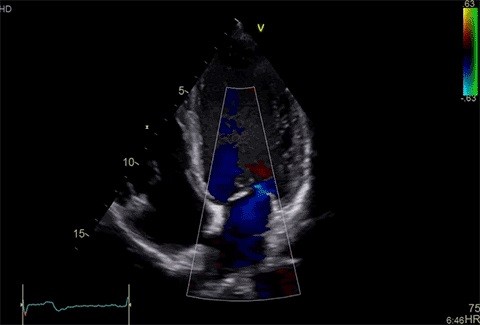

Kombinací vysokého výkonu produktové řady Vivid s výkonnou softwarovou platformou se Vivid S70 posouvá na zcela novou úroveň - poskytuje vynikající kvalitu obrazu srdečních aktivit. Díky 19palcovému širokoúhlému HD LCD displeji a 12palcovému širokoúhlému dotykovému LCD displeji zlepšují jeho ergonomii a intuitivnost. GE Vivid S70 poskytuje vynikající zobrazovací výkon spolu s moderní řadou sond XDclear.